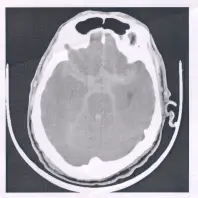

72歲男性,突然昏倒,送急診室,未注射對比劑之腦部電腦斷層( CT )檢查如圖,診斷是:

該圖為 72 歲男性昏倒後的非造影腦部 CT 之 axial 切面(基底顳部水平):

- 在顱底 Basal cisterns(包括 Suprasellar cistern、Ambient cistern)及左右 Sylvian fissures 可見多發條狀、片狀高密度影(血液)沿蛛網膜下腔分佈;

- 顱骨內側未見透鏡狀或新月狀高密度血腫塊,也